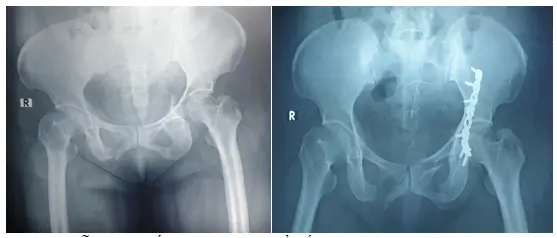

Phẫu thuật kết hợp xương vỡ ổ cối, trật khớp háng bên trái